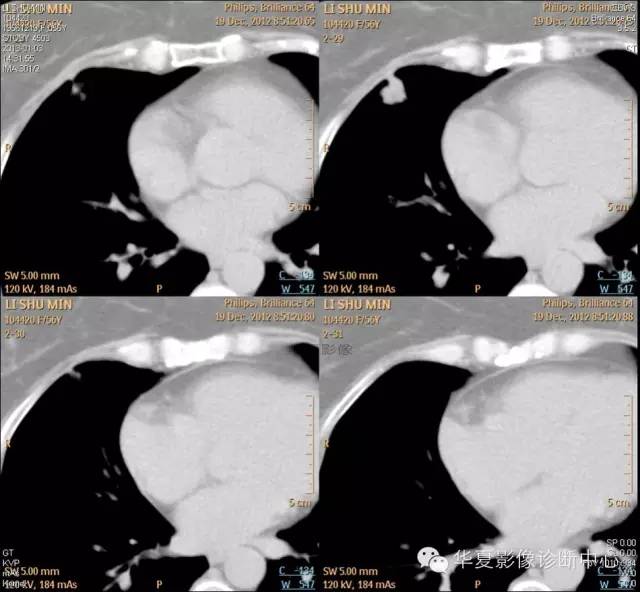

【病例学习】典型周围型肺癌CT病例一例

女,56岁,其父因肺癌去世,自觉胸部疼痛不适来诊要求拍胸片。

1.右肺上叶:肺组织1块,大小13×4×7cm。切面棕红色。2.右肺上叶肿物:灰白色组织一块,大小3×1×1.5cm。切面灰白色。3.右肺中叶结节:灰白色绿豆大组织1块。4.淋巴结:灰黑色绿豆大组织1块。

(右)肺中分化鳞状细胞癌。浸及胸膜。支气管残端切净。淋巴结未见癌转移(0/10)。